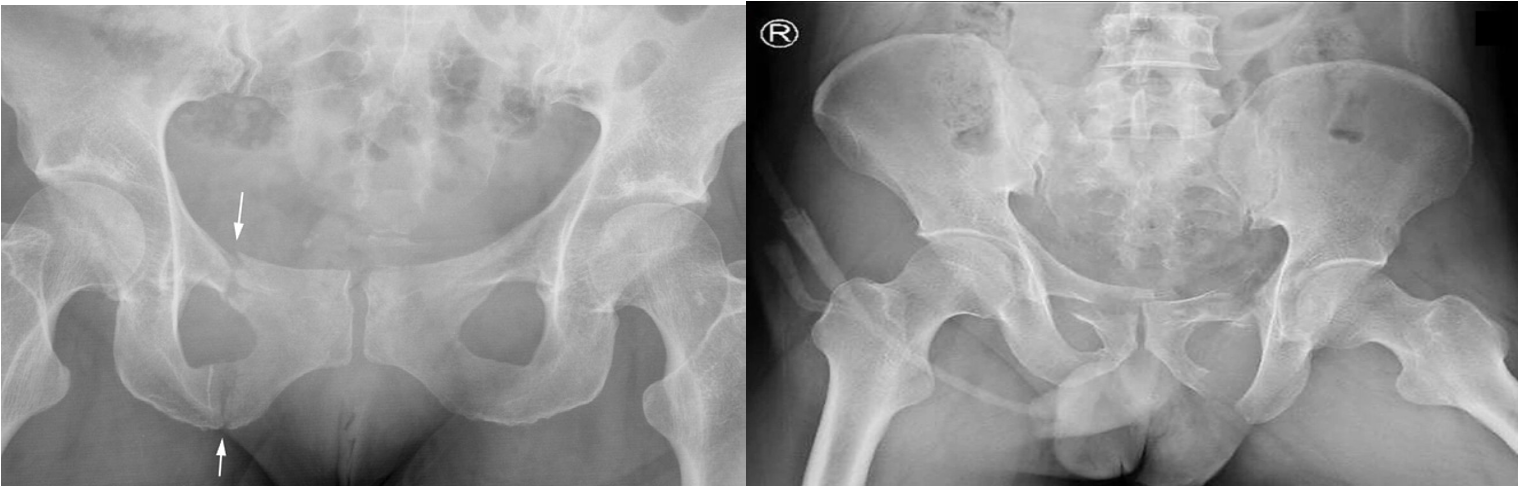

A. Fractures through the pubic rami (arrows) are common in the elderly.

B. Unstable pelvic ring fracture - X-ray pelvis (AP view) The right hemipelvis is displaced superiorly, compatible with disruption of the sacroiliac joint . Bilateral pubic ramus fractures are also present. - best to assess urethra after incident